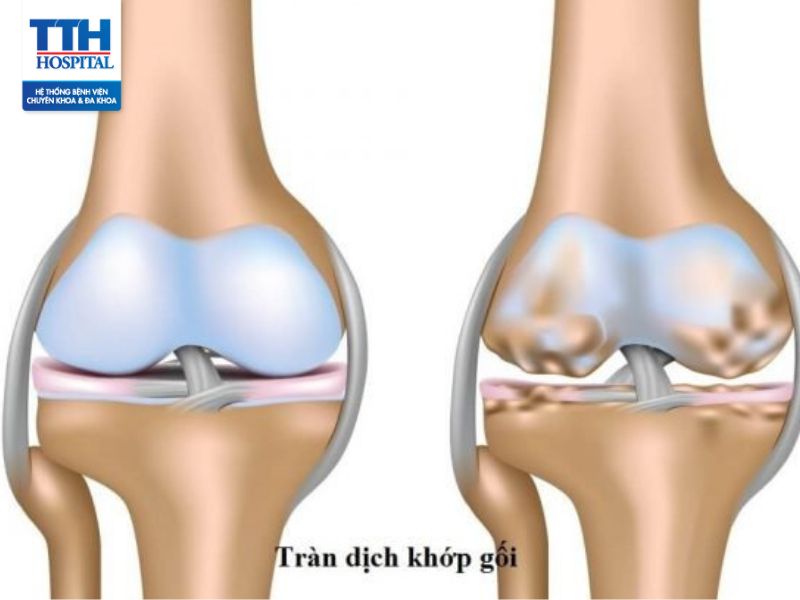

Tràn dịch khớp gối là tình trạng gia tăng lượng dịch bất thường trong khớp gối sau chấn thương hoặc các nguyên nhân bất thường trong khớp làm hạn chế vận động khớp gối.

Tràn dịch khớp gối là tình trạng gia tăng lượng dịch bất thường trong khớp gối sau chấn thương hoặc các nguyên nhân bất thường trong khớp làm hạn chế vận động khớp gối. Mặc dù không phải là một bệnh khó chữa nhưng nếu không được chẩn đoán và điều trị sớm có thể dẫn tới các biến chứng nguy hiểm.

Dấu hiệu tràn dịch khớp

Dấu hiệu cơ bản nhất để phát hiện tràn dịch khớp gối là tình trạng khớp gối nổi mẩn đỏ kèm sưng và phù nề, khi so sánh 2 bên khớp gối có thể nhận ra sự lớn hơn bất thường của bên tràn dịch do bao khớp dày lên. Bệnh nhân thường sẽ có cảm giác nặng nề bên khớp tổn thương và rất hạn chế vận động khi đi lại hoặc khó gấp duỗi. Theo thời gian nếu không được can thiệp thì các cơ xung quanh sẽ yếu dần khiến khớp ngày càng không vững cùng với cơn đau dai dẳng.